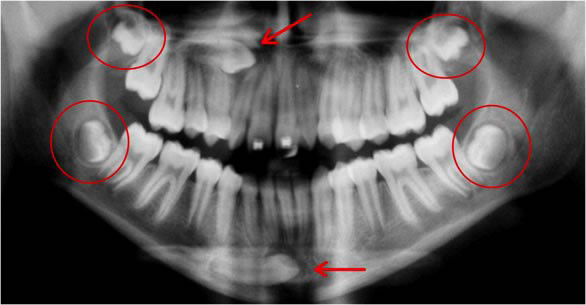

EXODONTIA DE 3º MOLARES (SISO)

O último dente a se desenvolver e erupcionar na boca é o 3º molar. Normalmente erupcionam aos 18 anos. Geralmente os 3º molares não tem espaço para erupcionar sendo indicada sua extração, sejam por fins ortodônticos ou profiláticos, para evitar problemas futuros como a reabsorção dos 2º molares, cistos e tumores, entre outros. Estes dentes podem erupcionar parcialmente dificultando a limpeza, acumulando alimentos, placas e bactérias na gengiva sobreposta o que pode resultar em cáries, doenças gengivais, abscessos e infecções não só nos 3º molares como nos dentes vizinhos. Os sisos podem ser extremamente problemáticos, sendo necessária a intervenção de um especialista Buco-Maxilo para sua remoção.